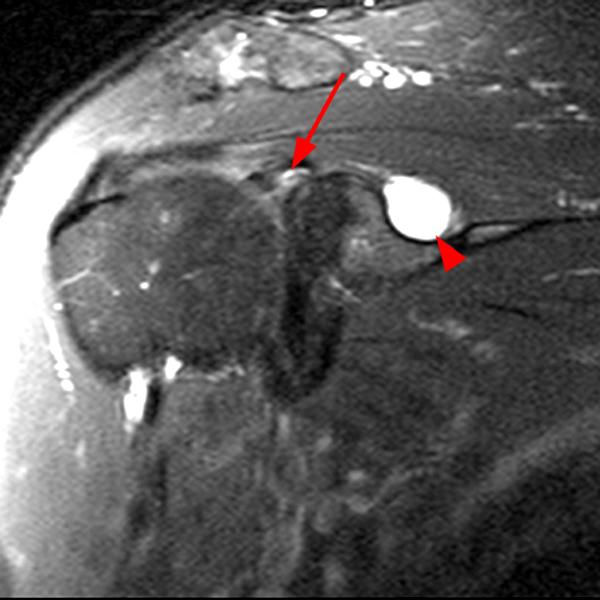

Shoulder Cysts Mri

From radsource.us

Shoulder Cysts Radsource Back Shoulder Cyst It's important to pay attention to the lump on your shoulder and its associated symptoms to determine if you should seek medical attention. Lumps on the shoulder are often associated with traumatic events, however, causes can also be inflammatory, cancerous, or environmental. They can develop anywhere around the shoulder but are the most common type of cyst on back of. Back Shoulder Cyst.